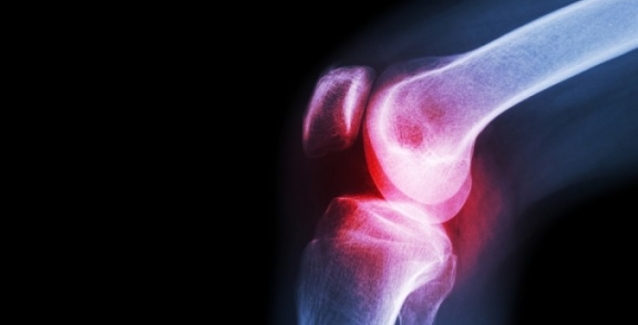

Όταν υπάρχει φλεγμονή στις αρθρώσεις, με αποτέλεσμα αυτές να σκληραίνουν και να πρήζονται, ο πόνος μπορεί να γίνει πραγματικά ανυπόφορος.

Υπολογίζεται ότι 1 στους 5 ενήλικες αντιμετωπίζει κάποια από τις περίπου 100 ιατρικές παθήσεις που επηρεάζουν το μυοσκελετικό σύστημα και ειδικά τις αρθρώσεις, όπου συναντώνται δύο ή περισσότερα οστά.